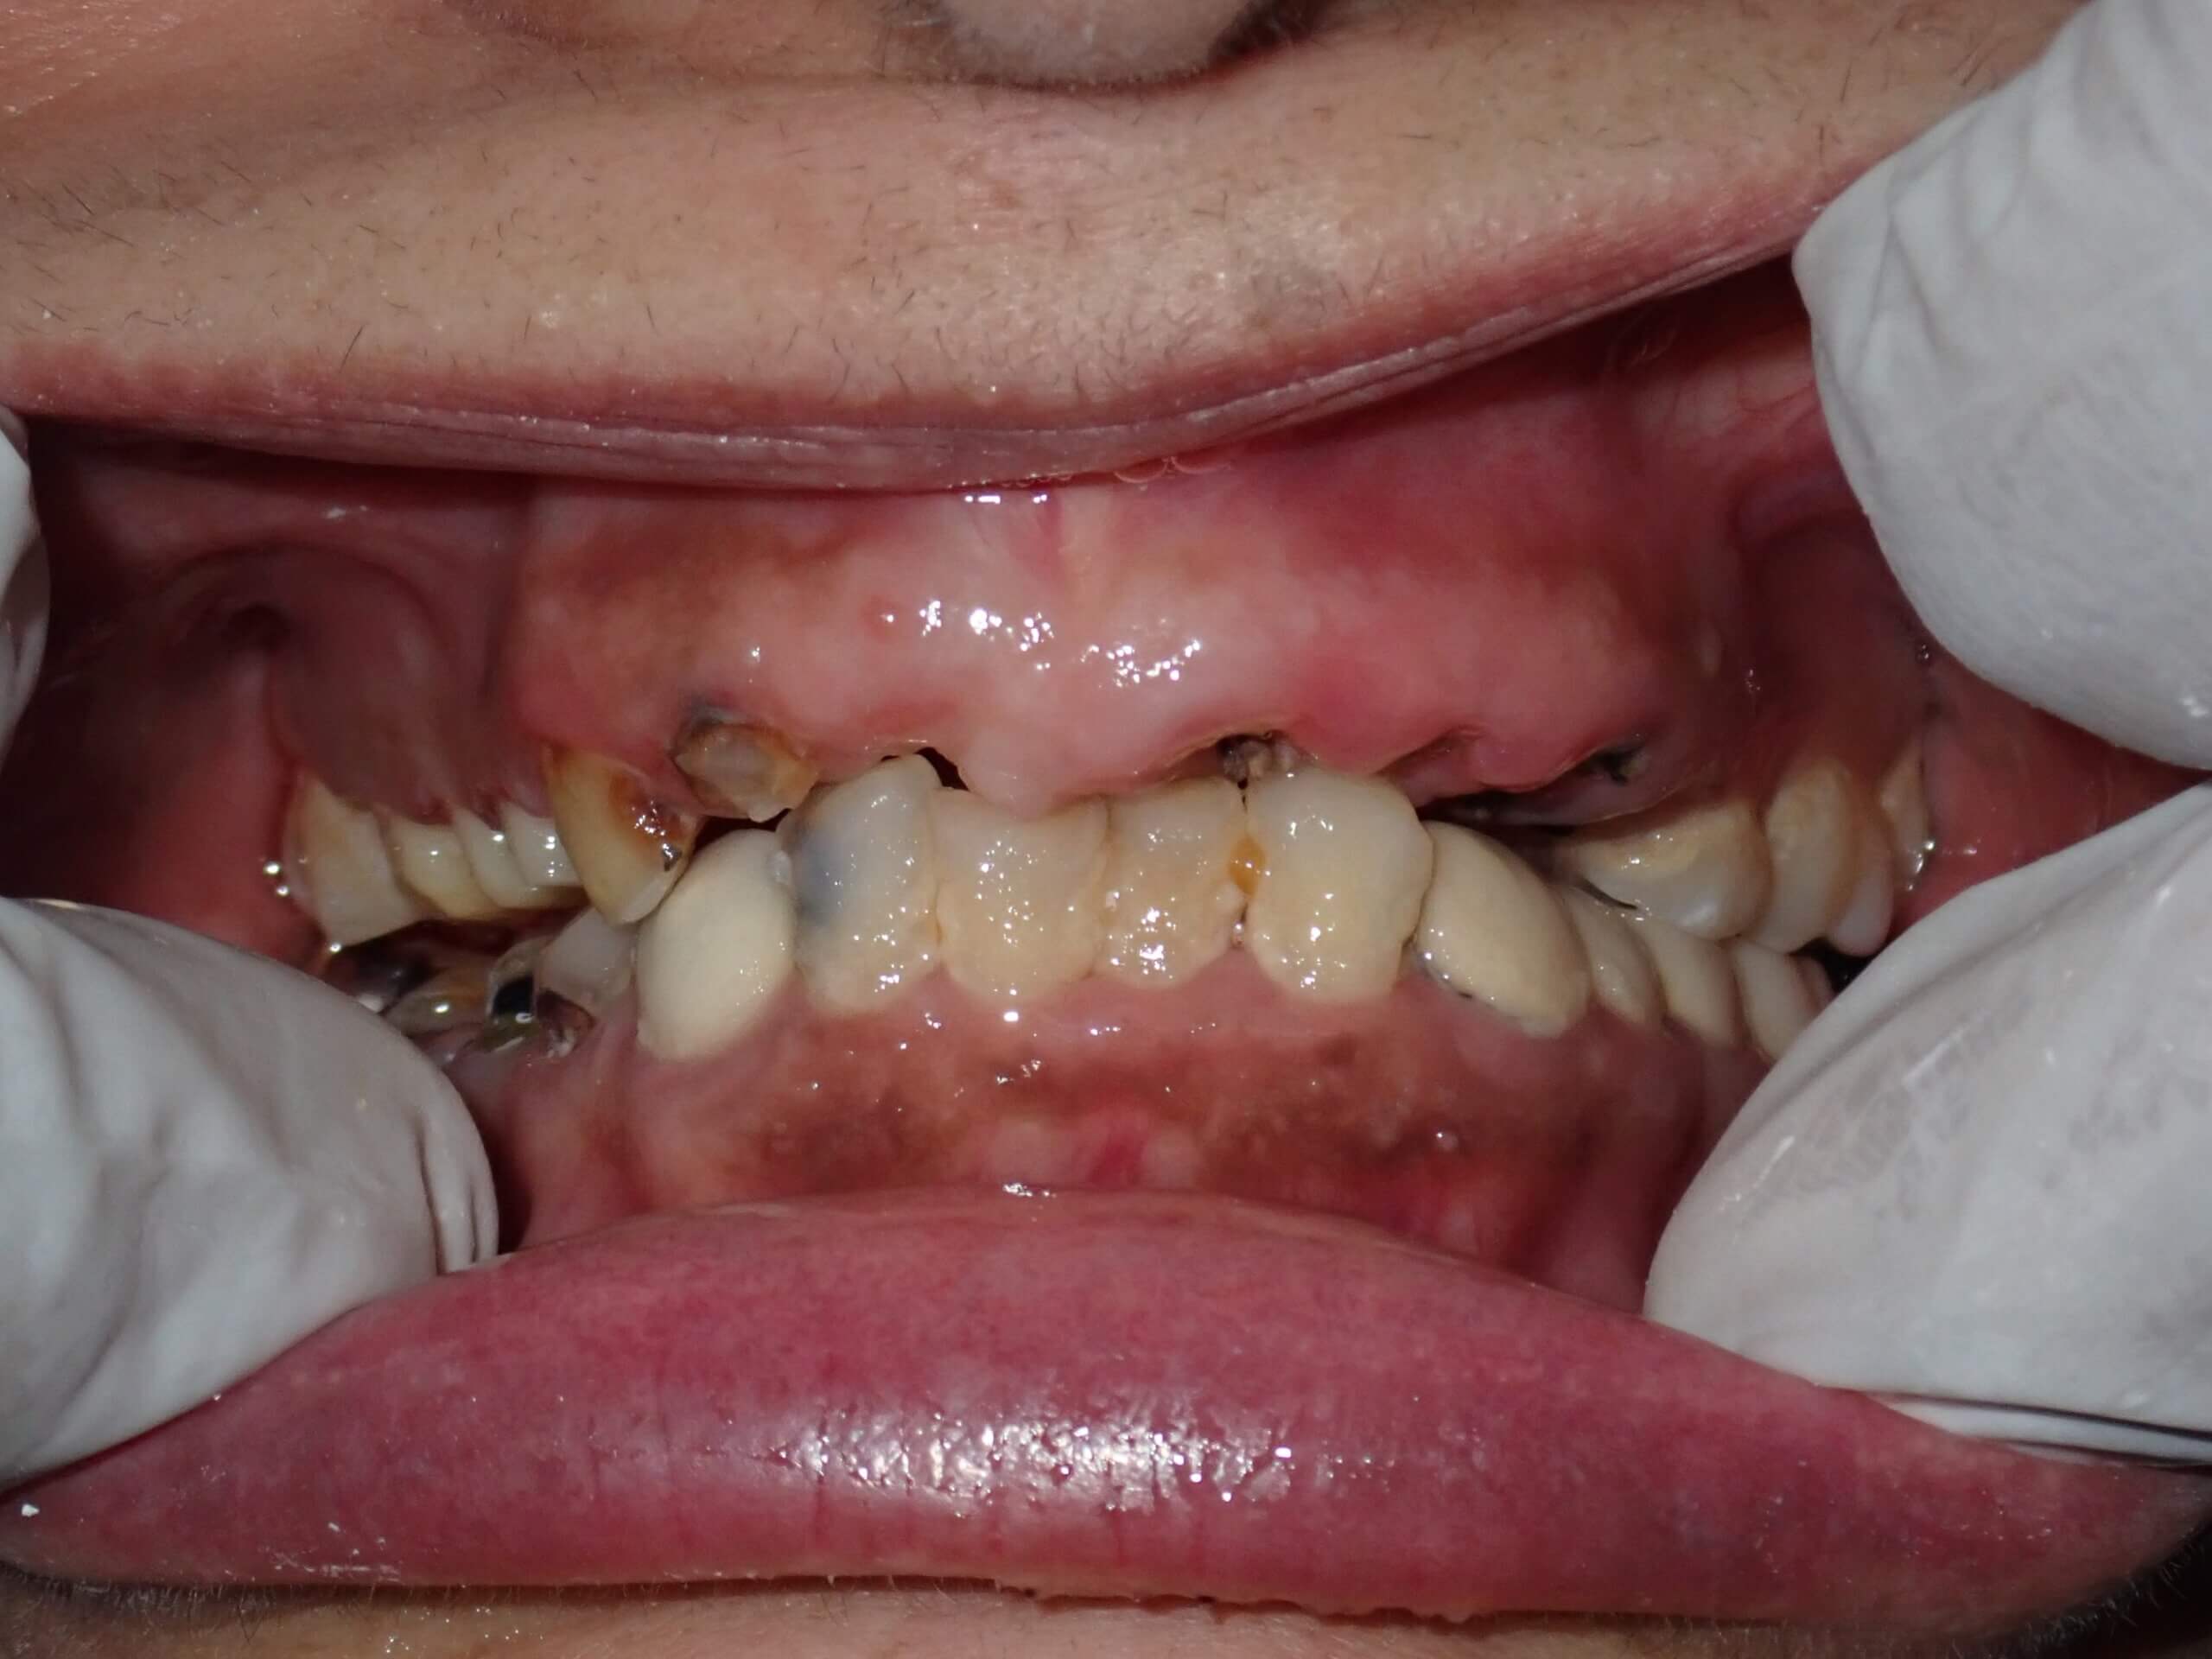

Sushma Sethi India Pre Treatment 20240806

Before

INITIAL ASSESSMENT & DIAGNOSIS: A detailed clinical examination, along with digital X-rays, revealed multiple compromised teeth with deep decay and infection. Several teeth had pulpal involvement requiring root canal treatment, while others showed structural damage and discoloration.

Key findings included:

• Multiple decayed teeth with nerve involvement

• Poor bite alignment affecting chewing efficiency. A collapsed bite.

• Missing and non-restorable teeth requiring extraction

• Generalized wear and discoloration

• Food lodgement due to spacing and improper contacts